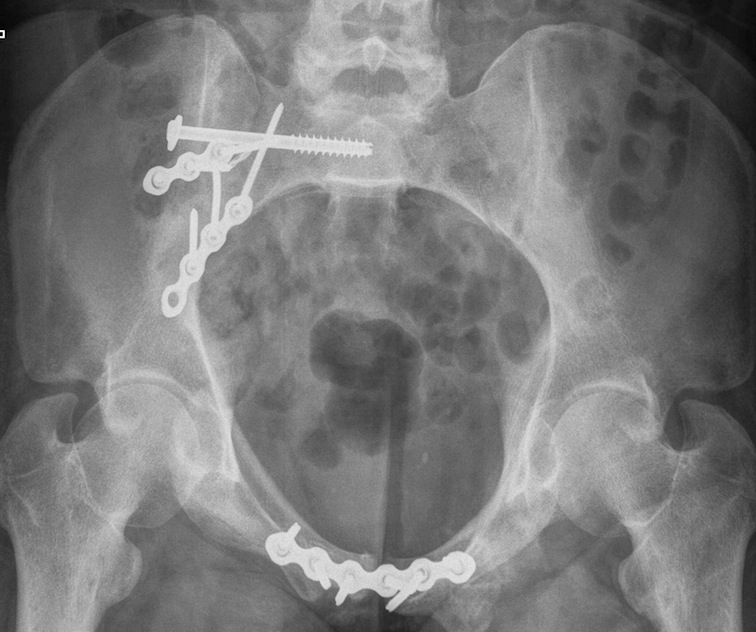

Posterior fixation

Percutaneous sacroiliac screws

Posterior approach + / - plates

Posterior sacral plates

Technique

- patient prone

- vertical incision 1 cm lateral to PSIS

- from crest to sciatic notch

- incise and reflect G maximus

- apply transverse plate

- soft tissue can be a problem

Anterior fixation

Indications

- instability following posterior fixation

- bilateral pubic rami fractures

Options

- plate - modified stoppa

- percutaneous ramus screws

- external fixation

LC-1 with anterior external fixation Plating of bilateral pubic rami fractures